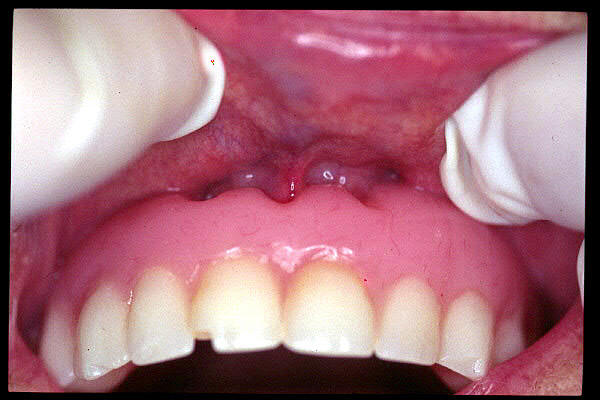

CM Hiperplasia gingival por prótesis

CM Hiperplasia por prótesis